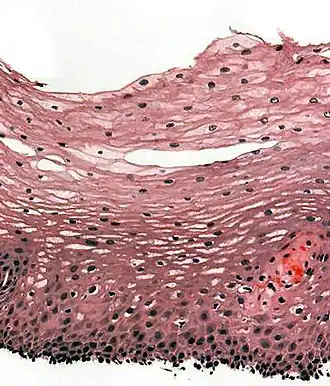

Section of the human skin showing the stratified squamous epithelial surface, referred to as the epidermis. The layer of keratin here is named the stratum corneum.

In the epidermis of skin in mammals, reptiles, and birds, the layer of keratin in the outer layer of the stratified squamous epithelial surface is named the stratum corneum. Stratum corneum is made up of squamous cells which are keratinized and dead. These are shed periodically.